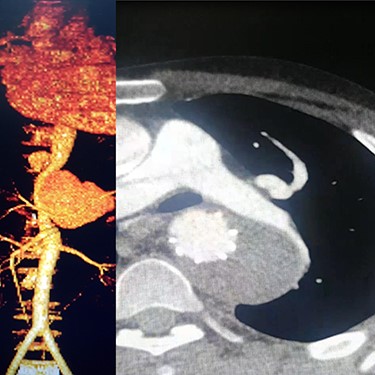

Case 2 — A 32-year-old man with known BD for years, presented to the emergency department with chest pain. We identified left subclavian and thoracic aorta saccular aneurysms on CTA (Fig. 2). Endoxan (1 gr) and Methyl prednisolon pulse (1 gr daily up to 3 days) were injected. The patient underwent a subclavian stent-graft (Fig. 3A) and elective TEVAR (Fig. 3B). Immediate follow-up angiogram revealed the luminal aperture was obtained and it was observed that the pseudoaneurysm remained occluded without a sign of leakage or endoleak. Tablet of prednisolon (5 mg) was prescribed twice daily.

(A) Angiography after stent-graft placement of left subclavian (right), (B) thoracic aorta (left).